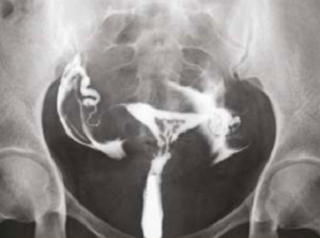

What does HSG assess?

-

Shape of the uterus

Normal shape

Unicornuate uterus

Complete septate uterus

Patency of fallopian tubes

Open tube

Closed tube

Uterine cavity

Clear/Normal

Submucosal fibroid

Adhesions/Synechiae